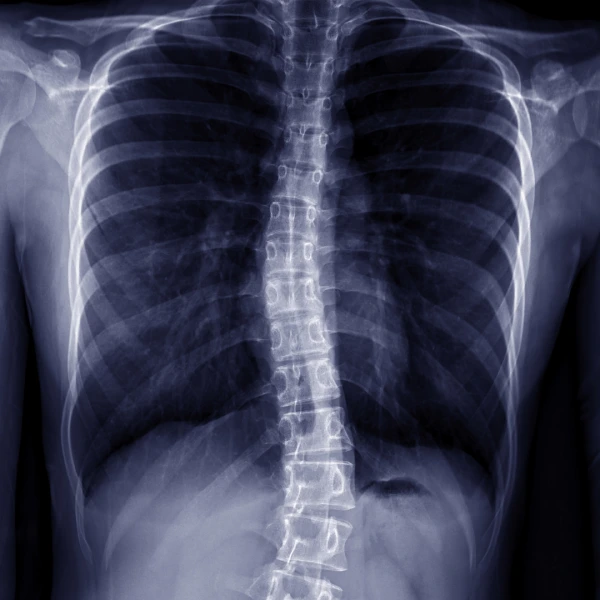

اسکولیوز یا قوز جانبی یک ناهنجاری اسکلتی است که با انحراف جانبی ستون فقرات به یک طرف بدن مشخص میشود. این انحراف به شکل غیرطبیعی ستون فقرات، آن را شبیه حرف انگلیسی “C” یا در موارد پیچیدهتر، شبیه حرف “S” میکند. این خمیدگی غیرعادی اغلب با چرخش مهرهها (Rotation) همراه است و موجب برآمدگی دندهها یا عدم تقارن در شانهها و لگن میشود. هرچند این عارضه در هر سنی ممکن است رخ دهد، اما شایعترین نوع آن یعنی اسکولیوز ایدیوپاتیک نوجوانان، در دوران بلوغ و رشد سریع مشاهده میشود که نیازمند توجه و تشخیص سریع است.

این اختلال نه تنها میتواند بر ظاهر فیزیکی و وضعیت قامت فرد تأثیر بگذارد، بلکه در موارد شدیدتر، ممکن است به عملکرد ریهها و قلب فشار وارد کرده و باعث درد مزمن شود. در کلینیک ارتوپدی فنی اورتومونتو، ما اهمیت این تشخیص زودهنگام را درک میکنیم و بر این باوریم که با اقدامات درمانی تخصصی و غیر جراحی مانند استفاده از بریسهای سفارشی در زمان مناسب، میتوان پیشرفت این انحراف را به طور مؤثری کنترل و تا حد زیادی اصلاح نمود و از جراحیهای بزرگ پیشگیری کرد.